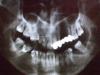

klk Опубликовано 3 июля, 2009 Автор Поделиться Опубликовано 3 июля, 2009 (изменено) Здравствуйте!Ситуация с зубами у меня ужасная. 11-живой зуб12-"ушла" десна (после удаления 13 оголился зуб)13-был удален,т.к.ретенированный14-вообще не было15-развернутм/у 15 и 16 зубами щель 0,3-0,5 см примерно 21-25-м/к мост,из них 21,22-сточены23,24-удалены25-сточенВыглядит все это вот так.Подскажите,как лучше сделать "зону улыбки",в частности что делать с 12,15 зубами? Изменено 3 июля, 2009 пользователем klk Ссылка на комментарий

klk Опубликовано 3 июля, 2009 Автор Поделиться Опубликовано 3 июля, 2009 (изменено) Вот фото! Изменено 3 июля, 2009 пользователем klk Ссылка на комментарий